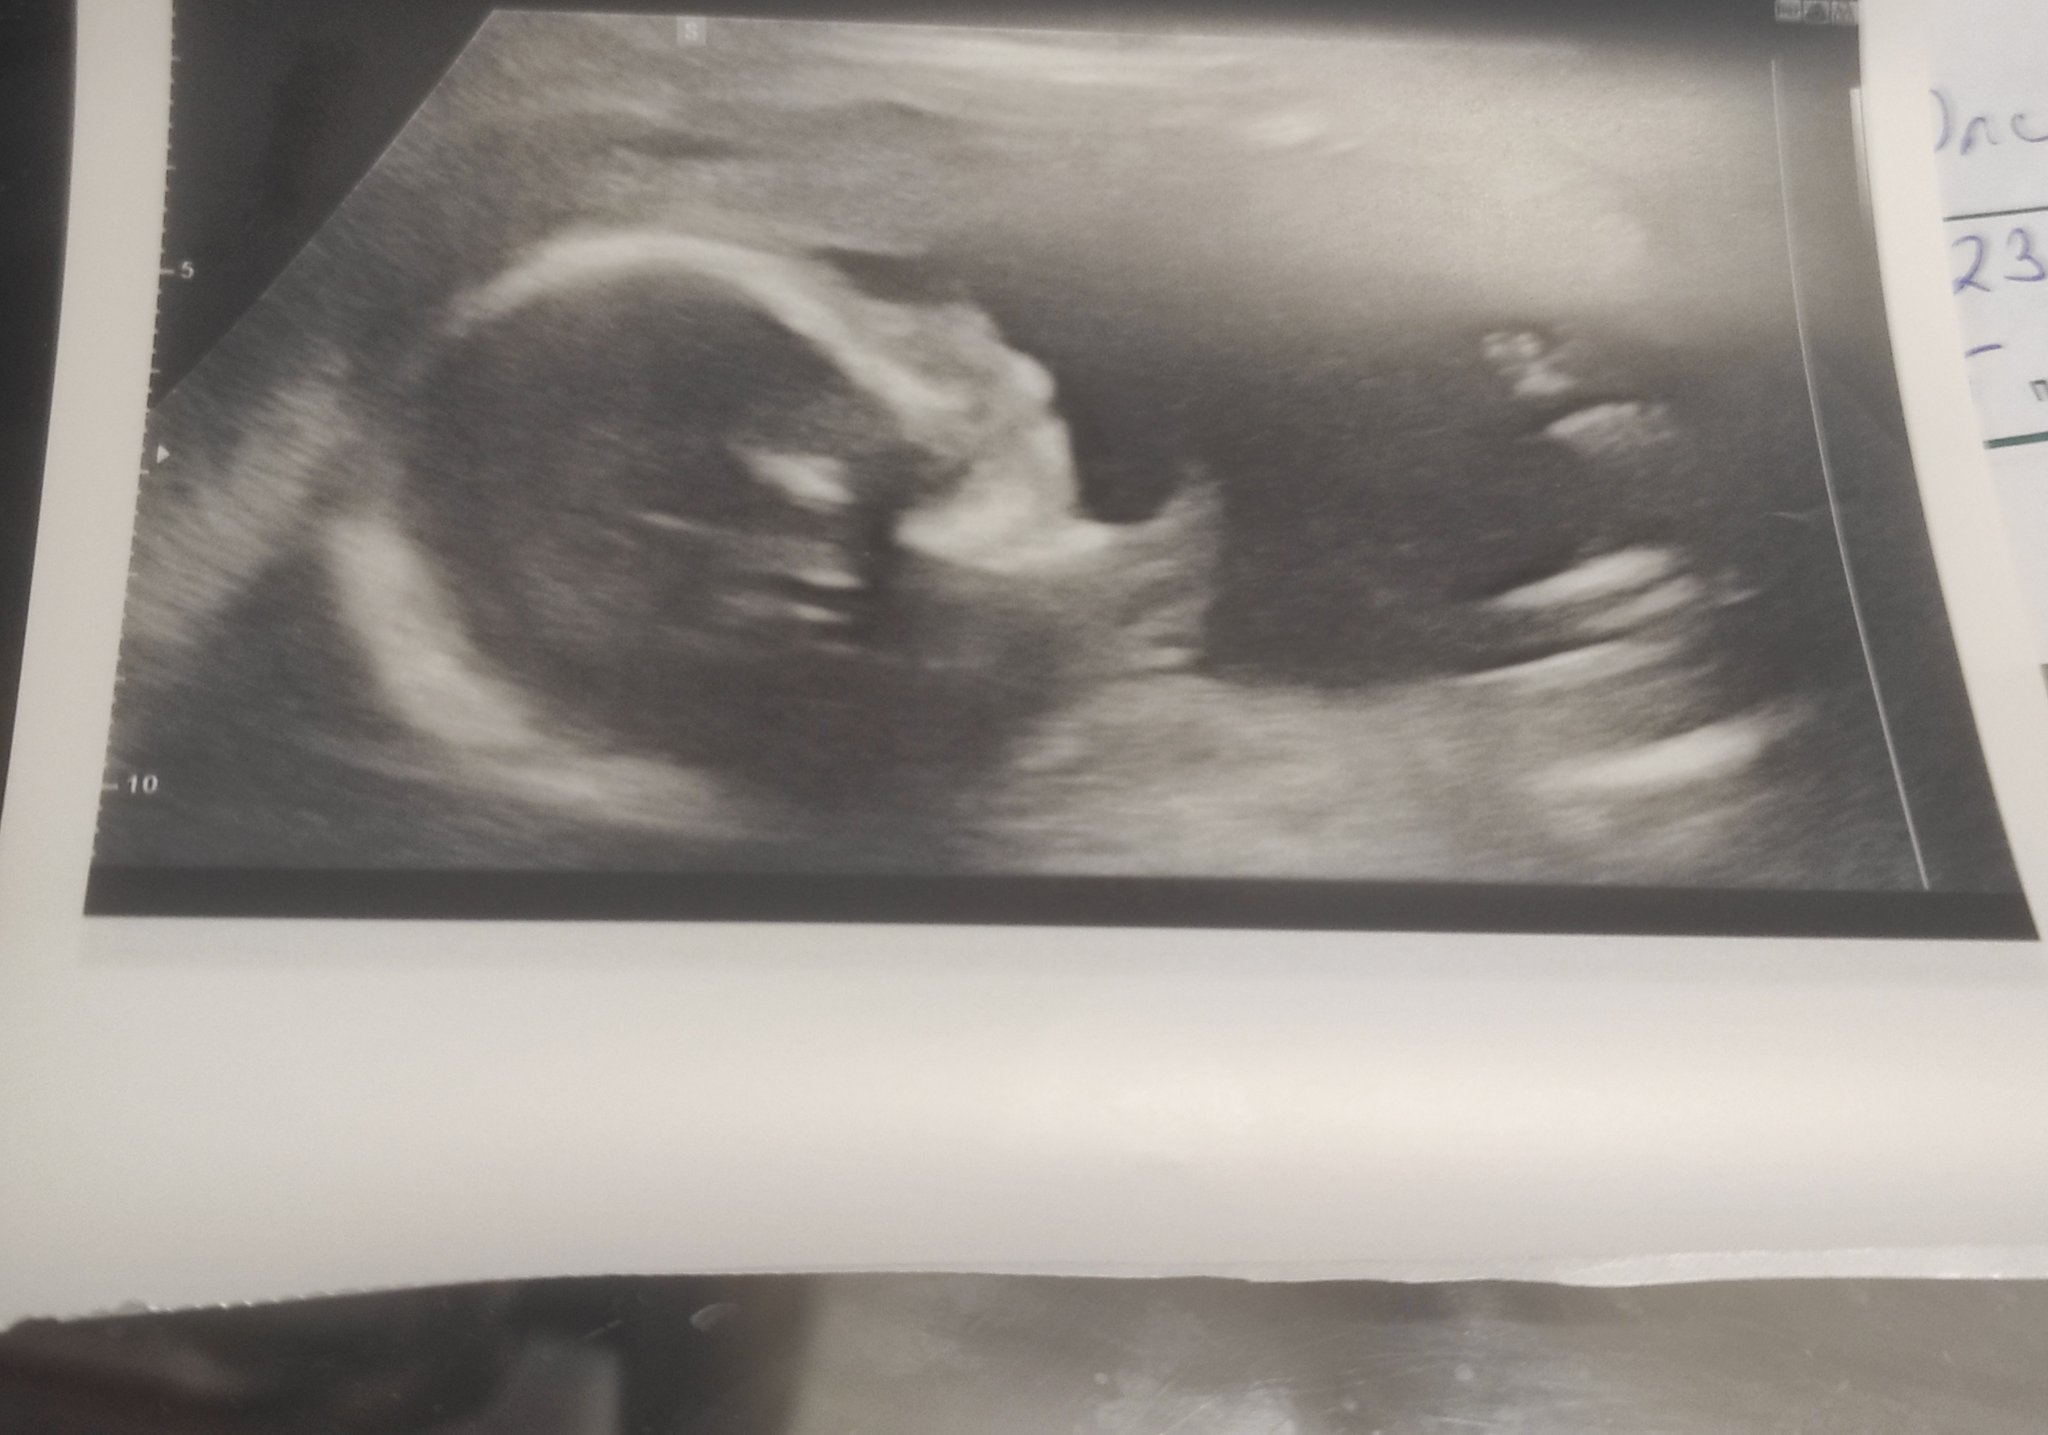

Мами вижте и моя снимка ,хем искам да се похваля ,хем нещо ме съмнява дали всичко е точно .

Понеже плод не виждам ....

Разбира се казаха ,че всичко е наред .

В 18 седм съм ,виждате ли нещо на снимката .

Вече съм 20 и от феталната снимките малко ме плашат ....

Мислих че ще са по друг начин ,дали си отговарят .

Особенно долната ...